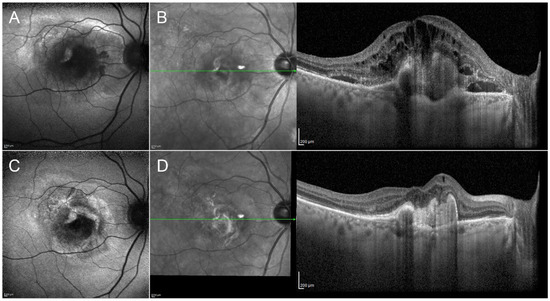

There is a general consensus regarding the efficacy and safety of anti-VEGF intravitreal injections in macular exudative and neovascular diseases (Figure 1) [54,55,56,57,58]. Owing to their relatively simple management and good tolerance, bevacizumab, ranibizumab and aflibercept are often used as a first line strategy. The main disadvantages regard the contraindication for patients at high cardiovascular risk and the large number of injections required, thus placing a considerable burden on public health systems. Brolucizumab recently obtained FDA approval for use in neovascular age-related macular degeneration [59] and Faricimab is due to obtain similar approval [60,61]; both drugs are currently being tested for other retinal diseases. All the other cited molecules are currently under investigation through multicenter clinical trials.

Figure 1. Clinical efficacy of anti-VEGF injections in macular neovascularization secondary to age-related macular degeneration. The onset of the neovascularization is characterized by evident changes of the fundus autofluorescence signal (A). Structural OCT describes a completely altered macular profile, with the presence of wide subretinal and intraretinal exudation (B). After the loading dose of three-monthly intravitreal injections of anti-VEGF, it is possible to observe an improvement of the fundus autofluorescence profile (C), together with the complete regression of the exudation detected by structural OCT (D).